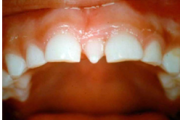

Turritavad ülemised lõikehambad.